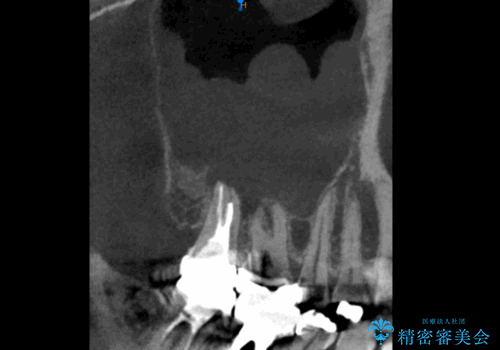

レントゲンと,CT撮影を行なったところ右上小臼歯が虫歯、右上第二大臼歯には根の先に大きな病気がありました。

根管治療はラバーダム防湿を行い、無菌的な状態で治療を行っています。

CTでは経過良好で経過観察を行なっていきます。